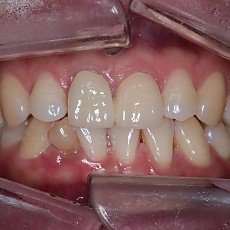

시술전후사진 12 페이지

Total 189건 12 페이지